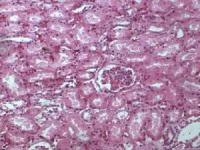

肾小管上皮细胞水肿